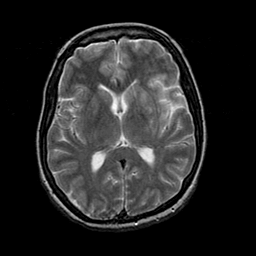

Acute Stroke: T2-weighted MR -- Slice #14

[Home][Help][Clinical][Tour 1] Slice 14